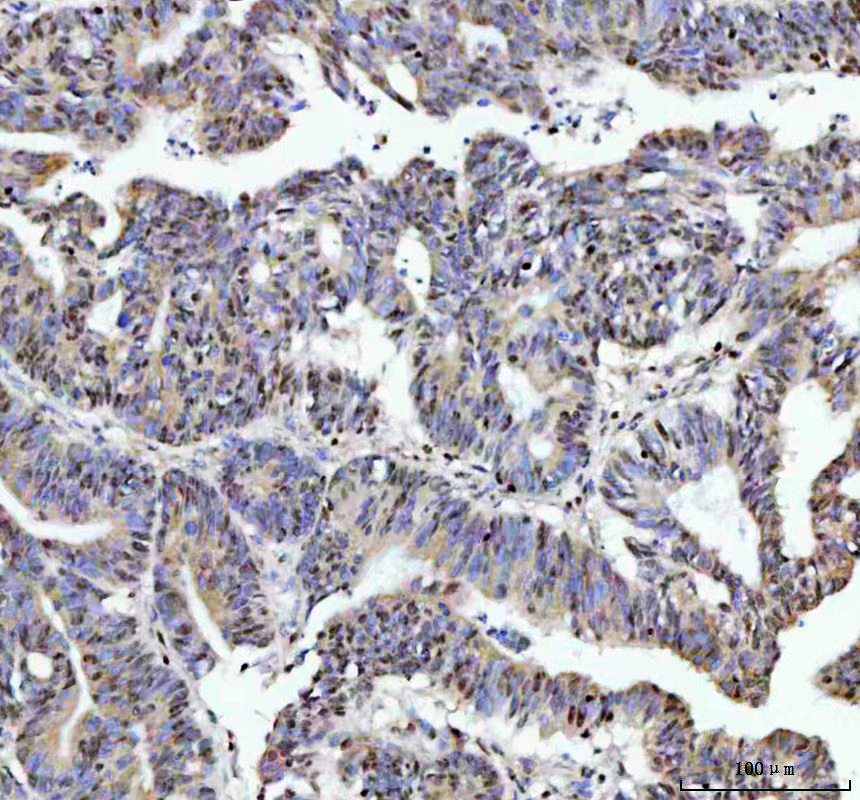

IHC analysis of FKBP5 using anti-FKBP5 antibody (BM5680) .

FKBP5 was detected in a paraffin-embedded section of human colorectal adenocarcinoma tissue. The tissue section was incubated with rabbit anti-FKBP5 Antibody (BM5680) at a dilution of 1:200 and developed using HRP Conjugated Rabbit IgG Super Vision Assay Kit (Catalog # SV0002) with DAB (Catalog # AR1027) as the chromogen.